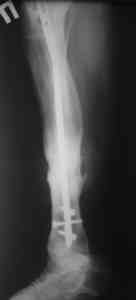

Вложение не в текстовом формате было извлечено…

Имя     : 5.jpg

Тип     : image/jpeg

Размер  : 26270 байтов

Описание: отсутствует

Url     : http://weborto.net:8080/pipermail/ortho/attachments/20080516/529c86f2/attachment-0006.jpg